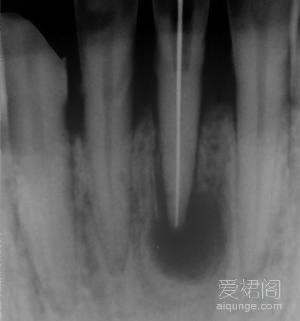

一个典型的根尖囊肿病例,对于这个患者来说,彻底的根管治疗是整个治疗过程的关键。首先,我们对这位患者进行了彻底完善的根管治疗,并要求患者在治疗过程中进行必要的抗炎治疗。患...